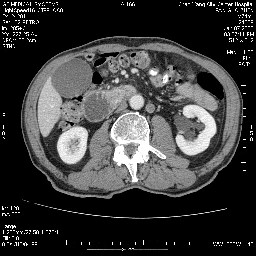

女,74岁,呕吐10余日

考虑来源于十二指肠水平段的恶性占位,侵及周围组织,特别是胰腺,可见区域淋巴结肿大,左侧下腔静脉畸形。

十二指肠水平段腔内占位伴梗阻,中等度较为均匀的强化,洗脱慢,区域淋巴结显示增多,符合腺癌表现。下腔静脉变异。

十二指肠降段扩张,水平段狭窄成鼠尾状,肠壁明显增厚,胰腺勾突增大成不均匀强化,其内可见低密度区,胆囊增大,1十二指肠水平段腺癌侵犯胰腺勾突可能大,2胰腺癌侵犯十二指肠(只有胆囊增大没有肝内外胆管扩张不好解释)代除外.

12指肠壁可见结节状隆起,考虑为12指肠腺癌并梗阻可能性大!

十二指肠水平部腺癌伴梗阻并侵犯邻近结构。下腔静脉发育变异。

十二指肠降段扩张,水平段狭窄成鼠尾状,肠壁明显增厚,胰腺勾突增大成不均匀强化,其内可见低密度区,胆囊增大,1十二指肠水平段腺癌侵犯胰腺勾突可能大,2胰腺癌侵犯十二指肠 。

今日手术结果:胰腺钩突癌侵犯十二直肠,腹腔淋巴结转移.